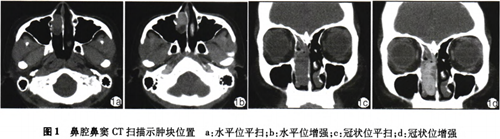

辅助检查:鼻窦CT平扫

+增强检查示右侧鼻腔内见团片状密度增高影部分充填,密度欠均匀,约 3.0 cm×1.3 cm×3.7 cm大小,与邻近鼻甲、鼻中隔

紧贴,骨质未见明显破坏征象,增强后实质部分明显强化,内见低密度无强似轻度强化区,诊断:右侧鼻腔肿物(出血坏死性息肉?血管瘤?其他)。考虑血管瘤可能性大(图1)。完善术前检查,于全麻下行右侧鼻腔新生物切除术,0.1%肾上腺素